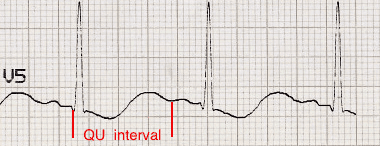

- Prominent U waves (best seen in the precordial leads V2-V3)

- Apparent long QT interval due to fusion of T and U waves (= long QU interval)

Hypokalaemia:

- Widespread ST depression and T wave inversion

- Prominent U waves

- Long QU interval

This patient had a serum K+ of 1.7